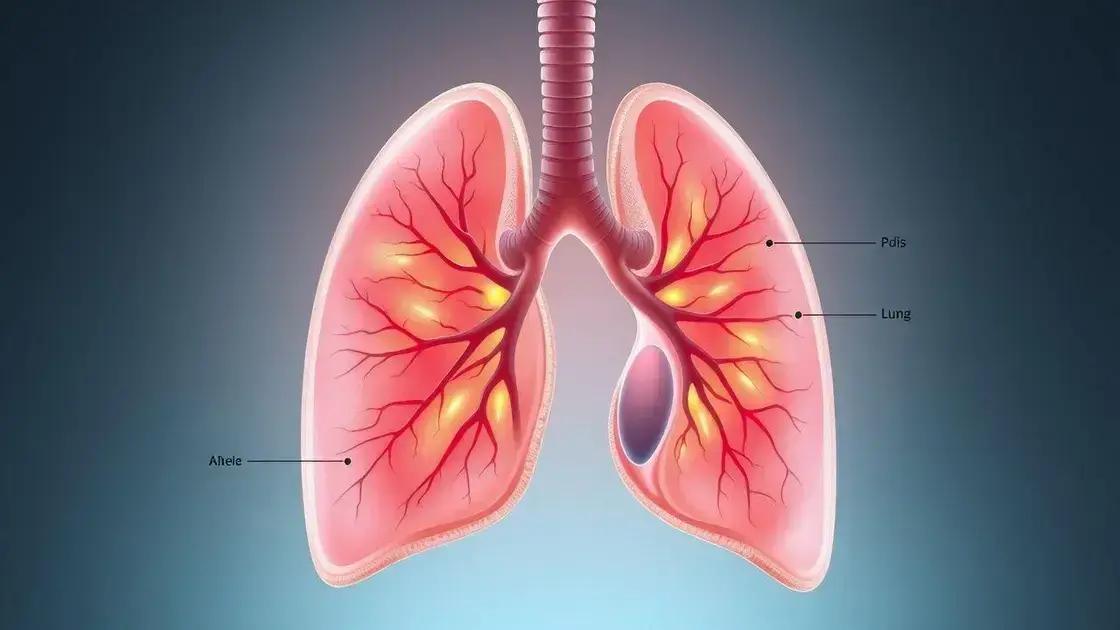

A pneumonia em crianças é uma infecção que afeta os pulmões, causando inflamação nos alvéolos pulmonares. Durante o inverno, essa condição merece atenção especial dos pais e cuidadores, pois o clima frio pode aumentar os riscos.

A pneumonia afeta diretamente a capacidade respiratória, dificultando a oxigenação adequada do corpo. Em crianças, isso pode ser especialmente preocupante devido ao sistema imunológico ainda em desenvolvimento.